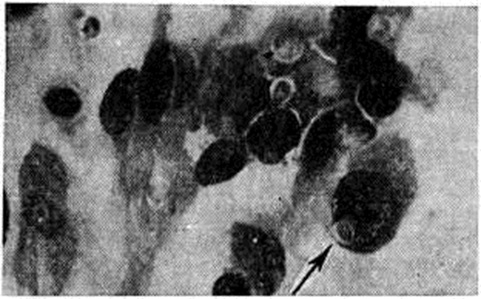

Кандидоз кожи проявляется в виде подострых дерматитов в складках кожи, изредка с образованием абсцессов и изъязвлением. При гистологический исследовании отмечается межклеточный отёк эпидермиса, паракератоз, акантоз и прорастание нитей грибка в некротизированный эпидермис (рисунок 2). Воспалительная инфильтрация преимущественно из сегментоядерных лейкоцитов наблюдается в основном в дерме. Иногда наблюдается формирование ограниченных абсцессов с наличием распадающихся сегментоядерных лейкоцитов. Впоследствии образуются гранулемы, состоящие из лимфоцитов, эпителиоидных и гигантских клеток (рисунок 3).

Рис. 2. | ||